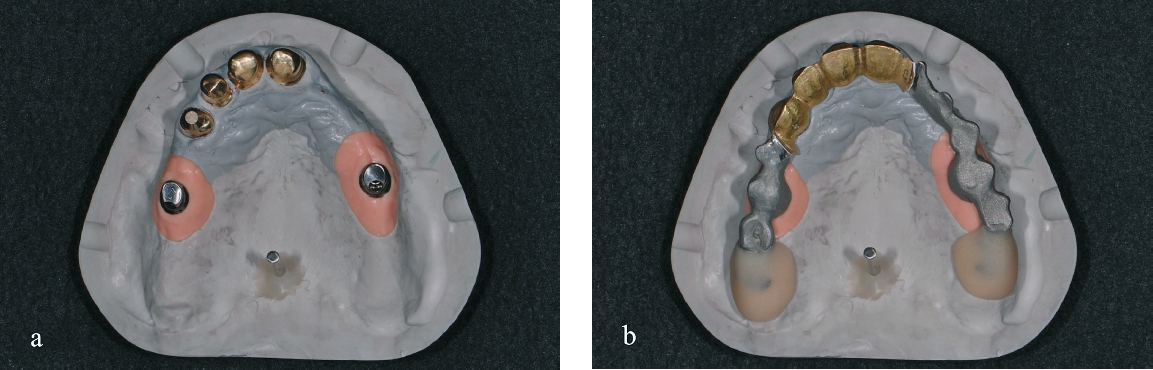

In einem nächsten Schritt wurden die Primärteile provisorisch fixiert und zusammen mit den Implantaten und den Schleimhautarealen überabgeformt (ImpregumTM, 3M) zur Herstellung des Meistermodells (Abb. 15). Die Position der Implantate wurde mittels „Verification Stent“ rückkontrolliert und die vertikale und horizontale Kieferrelation intraoral mittels Handbissnahme verschlüsselt. Aufgrund der nicht unerheblichen Achsendivergenz zwischen den Implantaten und den natürlichen Pfeilerzähnen wurde entschieden, die Implantate anstelle von konfektionierten Einzelelementen mit individuellen CAD/CAM-Teleskopkronen (Atlantis Abutments, Dentsply Sirona, Wals bei Salzburg, Österreich) zu versorgen. Konfektionierte Einzelelemente wären durch die Achsendivergenz einem erhöhten Verschleiß unterzogen gewesen, was wiederum mit einem gesteigerten Nachsorgebedarf verbunden gewesen wäre. Nach mehreren Set-up-Einproben konnte schließlich auch das Sekundärgerüst hergestellt werden. Sämtliche Sekundärteile wurden dabei als Vollgussteile designt und mit dem Modellgussgerüst verklebt, mit Ausnahme der Sekundärteile für die Implantatteleskopkronen, welche zur Sicherstellung der Passivität intraoral verklebt werden sollten (Abb. 16 u. 17). Sowohl Primär- als auch Sekundärteile wurden für eine höhere Härte während 30 min bei 400°C vergütet. Anschließend konnte das geschlüsselte Set-up und auf das Gerüst aufgepasst werden. Um die Pfeilerzähne wurde die Prothese offen gestaltet, um eine natürliche Umspülung der Pfeilerzähne zu ermöglichen. Auf ein Palatinalband konnte aufgrund der guten Kammverhältnisse und des breiten Unterstützungspolygons verzichtet werden. Nach einer letzten klinischen Einprobe konnte die Prothese durch den Zahntechniker individualisiert und fertiggestellt werden (Abb. 18).

Mittels Platzanalyse auf dem Modell wurde die notwendige Nachpräparation der Pfeilerzähne festgelegt und anschließend klinisch umgesetzt. Dentindefekte wurden vorher mit Komposit direkt aufgebaut (Abb. 10 u. 11). Es folgte eine einzeitig zweiphasige Meisterabformung der Pfeilerzähne mit PermadyneTM (3M, Neuss) und einem individuellen Löffel mit folgender Einprobe der Primärteile (Abb. 12–14).